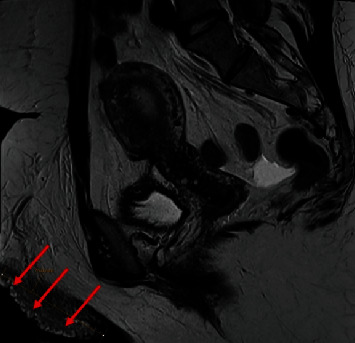

This case report describes an instance of vulvar lymphangioma occurring in the setting of May-Thurner syndrome (MTS), an association between two vascular conditions that we do not believe has been previously reported. Lymphangioma, also known as lymphatic malformation, is a benign lesion typified by dilatation of endothelial-lined lymphatic channels involving the skin and subcutis, which can occur either as a congenital abnormality or as a result of acquired damage to lymphatic channels. Lymphangioma is a rare lesion in the vulva. MTS, also known as iliac vein compression syndrome or Cockett's syndrome, is a condition of left iliac vein obstruction due to overriding the right common iliac artery which can lead to iliofemoral deep vein thrombosis. In this report, we describe the case of a 29-year-old woman with MTS diagnosed at 7 years of age with poor lymphatic drainage and pelvic pain requiring left iliac vein stenting. She presented with left vulvar discomfort and chronic lower extremity edema and was found to have warty vulvar masses, with histopathological examination showing lymphangioma of the vulva. We believe that this is the first report of vulvar lymphangioma recognized in the setting of MTS, and we will discuss the clinical features, etiology, and possible pathophysiologic association between these two entities.